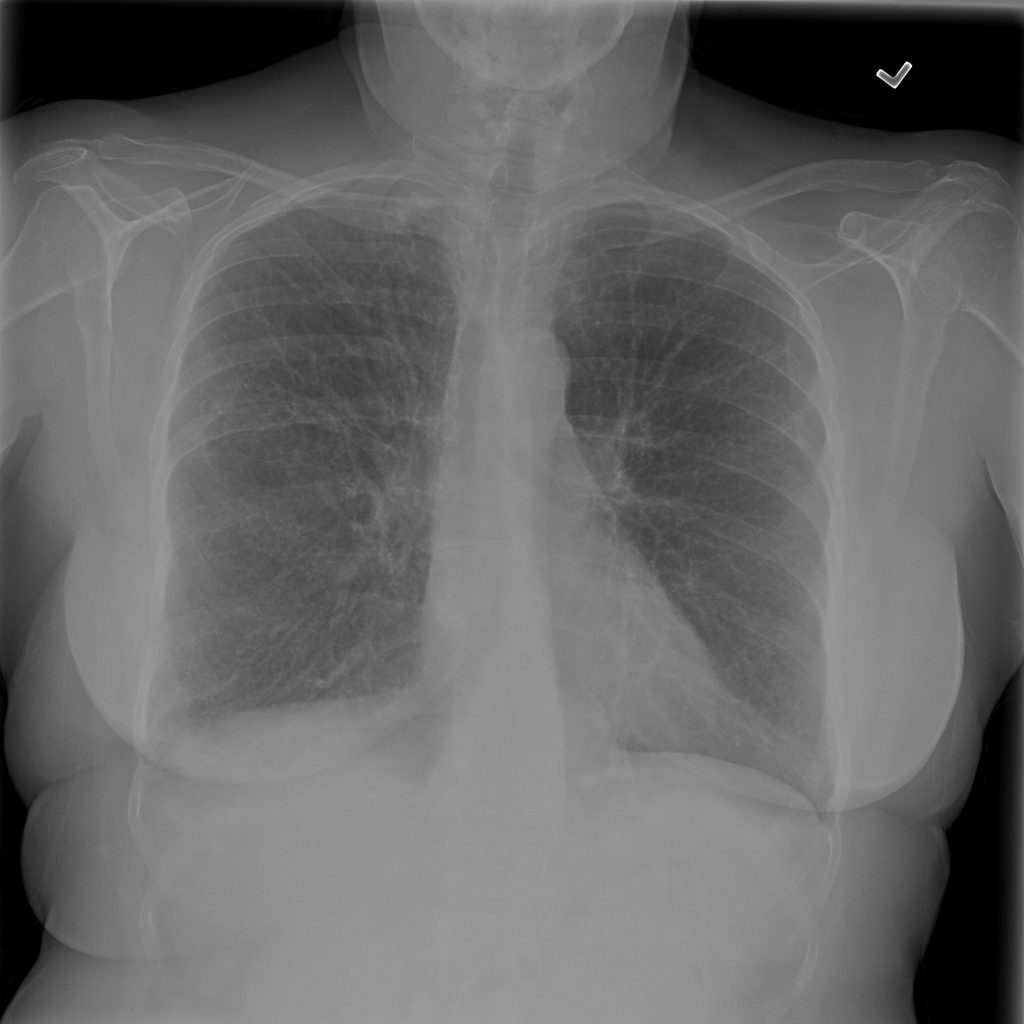

PAT-4F7E · IMG-000Hernia

PAT-4F7E · IMG-000

PA